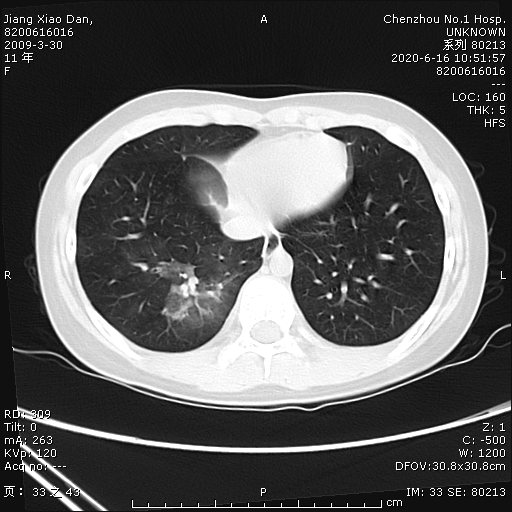

小單因?yàn)椤翱人?、吐?天,嘔吐1天”于6月11日到郴州市第一人民醫(yī)院就診,經(jīng)胃鏡檢查提示糜爛出血性胃炎,考慮“上消化道出血”,收入兒童醫(yī)院消化內(nèi)科住院治療。經(jīng)給予“阿莫西林、克拉霉素、奧美拉唑”聯(lián)合根治幽門螺桿菌治療,患兒仍咳出兩次鮮紅色血液混合粘液,考慮患兒并非單純上消化道出血,遂請(qǐng)兒童呼吸二區(qū)會(huì)診,擬“咯血查因”,轉(zhuǎn)入兒童呼吸二區(qū)繼續(xù)治療,入科后急行胸部血管成像cta檢查示右肺下葉肺出血改變,并未發(fā)現(xiàn)異常血管。右肺下葉支氣管后基底段鑄形軟組織密度影充填:支氣管腔內(nèi)積血?

為進(jìn)一步明確診斷,呼吸二區(qū)副主任醫(yī)師吳瓊給患兒行纖維支氣管鏡檢查,進(jìn)鏡時(shí)可見(jiàn)血液自聲門流出,進(jìn)鏡后發(fā)現(xiàn)右下葉外、后基底段開(kāi)口可見(jiàn)腫塊堵塞,是血凝塊填塞?還是新生物?可不可以鉗取組織明確腫塊性質(zhì)?術(shù)前的胸部血管成像cta并未發(fā)現(xiàn)異常血管,鉗夾是否安全?鉗夾后會(huì)不會(huì)導(dǎo)致大出血窒息?……一連串的問(wèn)題擺在在場(chǎng)所有的醫(yī)生護(hù)士面前,怎么辦?動(dòng)還是不動(dòng)?治療陷入了困局。